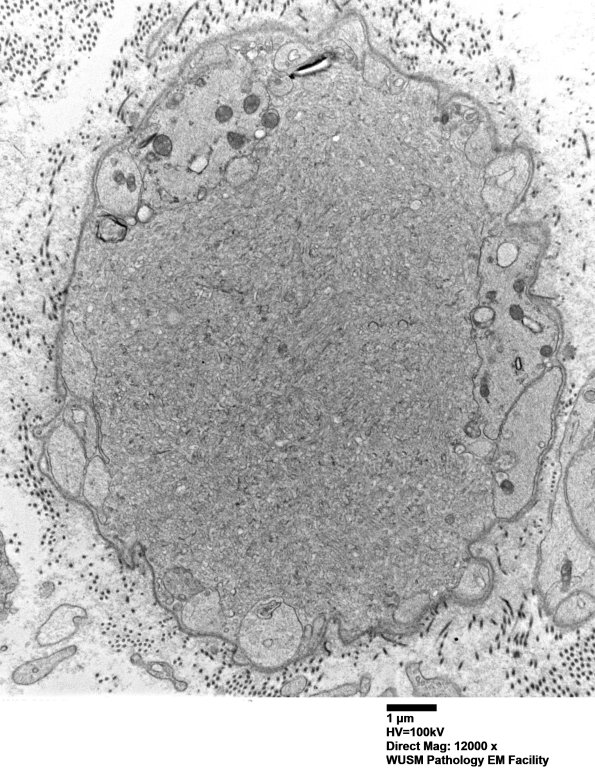

16C1-10 These spheroids have an ultrastructure unusual in my experience. Typical axonal spheroids contain large numbers of small vesicles, neurofilaments, mitochondria and other subcellular cytosomes. The structures in the current case do not contain rough endoplasmic reticulum, lipofuscin, pi granules, myelin elements or nuclei. Adjacent to these central elements are a periphery of Schwann cell processes, resembling a band of Büngner and, by inference, suggesting that these structures are related to regeneration of the axon and may represent growth cones, possibly elements which have been frustrated in their attempts at regeneration. These structures do not contain anastomosing tubulovesicular elements seen in dystrophic axons. I do not think that these structures contain myelin debris which has undergone vacuolar change or any structure normal for the PIN. (Electron micrographs)